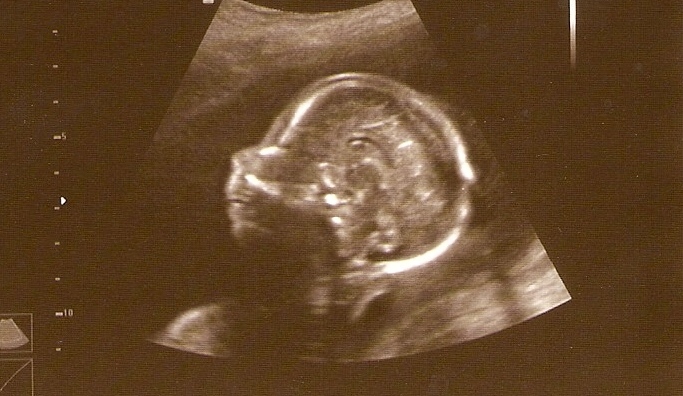

tak taky se pochlubím.. to je naše Kačenka... jen nevím jestli to bude kvalití fotka fotila jsem to do mobilu a pak do foťáku... kdyžtak zíta dodál lepší rozlišení

[136257] Verčo, trošku to vidět je, ale nejlepší je to naskenovat, to je pak úplně čisté....

. To je 3D, že? I trošku takto rozmazané to vypadá moc hezky. 3D rozlišení je na fotečku nejhezčí.

skener bohužel nemám.. ale zkusím to nějak vylepšit.. :-) Lucy prosím tě co si myslíš o těch pohybech mám plašit?? jsem z toho už doost nervózní